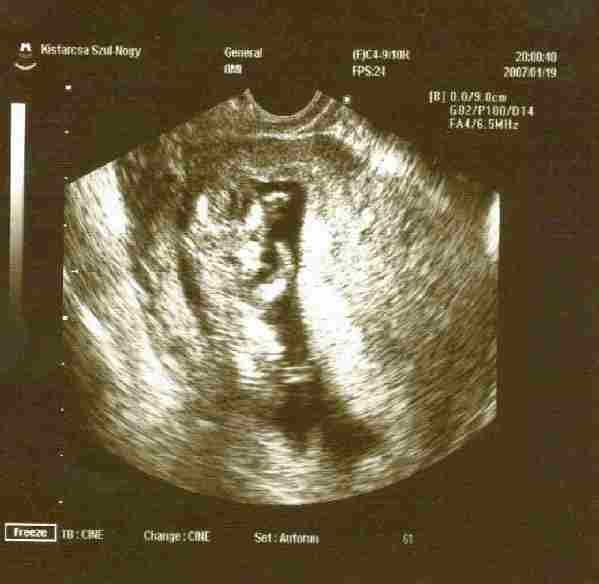

Csak egy gyors helyzetjelentés: tegnap voltam dokibácsinál, mindent a legnagyobb rendben talált, őszinte megdöbbenésemre életemben először nem volt gond a vérképemmel! Kismanó nyakiredőjét 2 hét múlva nézik, akkor majd kap apa egy szép képet is róla, hogy hurcolhassa a tárcájában, mert szegénykém eddig még nem láthatta legifjabb sarját a monitoron, ugyanis Bogi után kellett rohangálnia és nem tudott bejönni a rendelőbe. Mondta is, hogy így nem hiszi el, hogy van baba, de akkor meg mitől kerekedek annyira és vagyok rosszul rendszeresen :?: :lol: :lol: